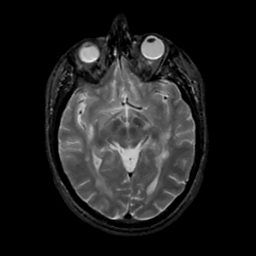

MR Study #10, April 28, 1991 -- Slice #22